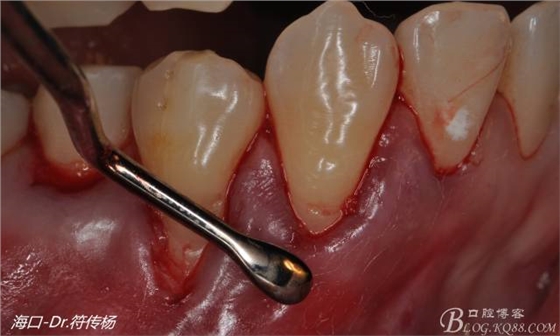

最后使用牙齦乳頭分離器分離牙齦乳頭